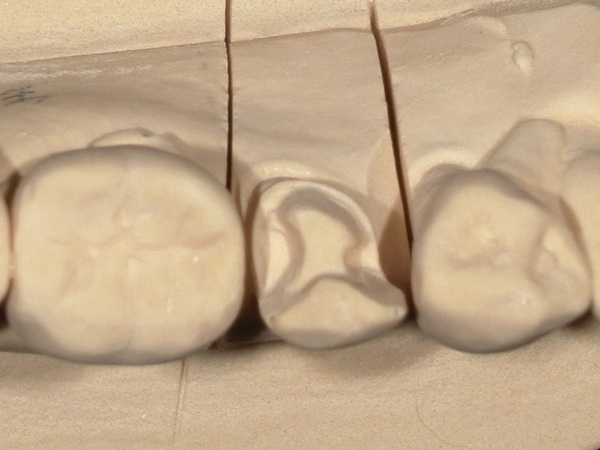

③型取り

歯の形を丁寧に整え、型取りを行いました。

こちらが完成したセラミックインレーです。